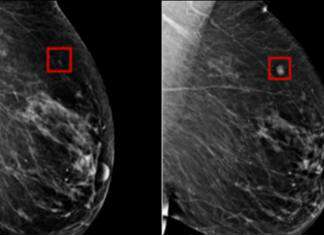

CNN's Poppy Harlow speaks with Dr. Larry Norton, the medical director of the Lauder Breast Center at the Memorial Sloan Kettering Cancer Center, about the use of artificial intelligence in breast cancer detection.

The post Images Show AI Detecting Breast Cancer 4 Years Before It Developed appeared first on The Seattle Medium.